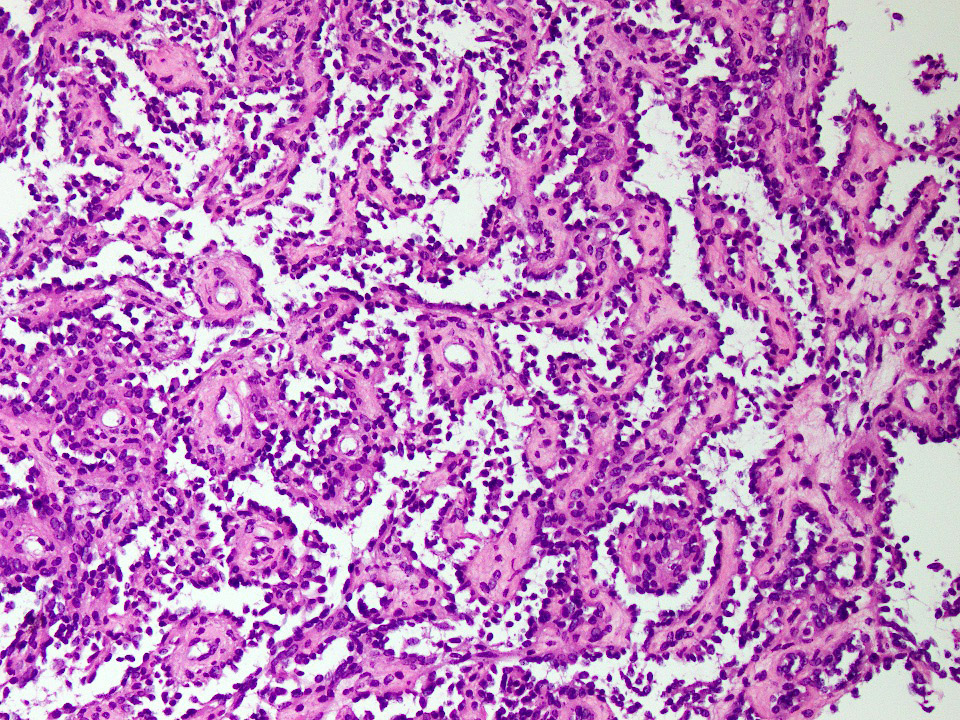

Microscopic (histologic) description

- Composed of elongated arborizing vascular channels that resemble rete testis, hence the name

- Endothelial cells are bland with hobnailed hyperchromatic nuclei

- Nuclear atypia is not seen

- Mitotic figures are rare

- Lesional stroma is fibrotic and shows lymphoid infiltrate (J Med Case Rep 2021;15:69, Int J Clin Exp Pathol 2010;3:528)

- Occasional cells with cytoplasmic lumina may be rarely seen (J Med Case Rep 2021;15:69)

- Occasionally, intraluminal papillary proliferation may be seen, resembling Dabska tumor (Hornick: Practical Soft Tissue Pathology - A Diagnostic Approach, 2nd Edition, 2018)

Microscopic (histologic) images